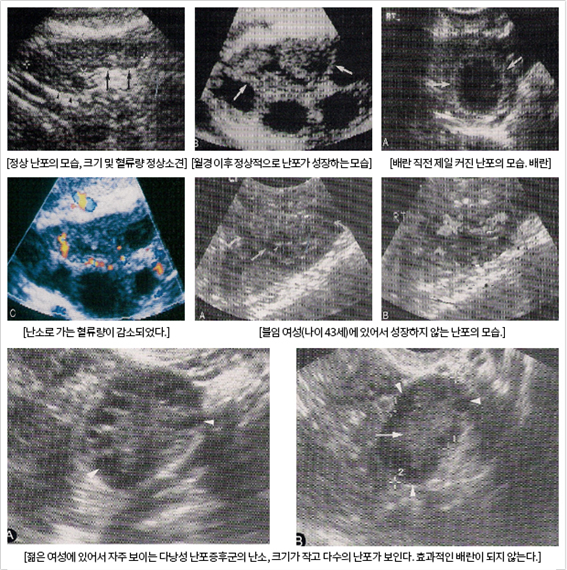

���ұ�ɰ˻�

������ ���̰� ���� ���� ���ҿ� �����ִ� ���ڵ鵵 ��ȭ�ϰ� �˴ϴ�. �̰��� ���ڰ� ���ڿ� ������ �� �ִ� �ɷ��� �������ٴ� ���� �ǹ��մϴ�. ������ ���� �����ϴ� �Ͱ� ���ÿ� ���� ���ϵ� ������ ���� �����ϸ鼭, �¾��� ����ü �̻��� ���� ���輺�� �������ϴ�.

30�� ������ ������ �ӽ��� �õ��� �� �Ѵ� �� �ڿ��ӽ��� �� ���ɼ��� ��������� �� 20%������, 40�� �̻��� ������ �ӽ��� ���ɼ��� �� 5%�� ��ǰ� �ֽ��ϴ�.

������ AMH�� ����ÿ��� ���� ���� �к��ϴٰ� ���ӱ� �ʱ ���� ���� ���� �к��ϰ� ���������� ���ҵǾ� ������Ŀ� ������� �ʾ� ���ұ�ɰ� ������ ������ ���̴� ������ �˷��� �ֽ��ϴ�.